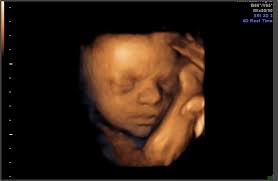

Pain in the abdomen and under the ribs can be caused by the growing uterus, which presses the internal organs. Your baby is now the size of a beetroot, measuring around 14 inсhes (35.6 cm) in length and weighing around 2 pounds (907 g). Baby is still working on putting on weight to get adorably chubby, and their eyes are looking around, though there's not enough pigment in the iris to determine eye color quite yet. 26 to 28 weeks (photos) every pregnant belly is different. Pregnancy checklist at 26 weeks.

The lungs are now starting to produce surfactant, which is a substance that helps the lungs inflate properly with each breath. Your baby still looks very lean, but he will gain fatty supplies and increase weight gradually throughout the remaining weeks of the pregnancy.   this week, baby weighs just about 32 ounces or 2 pounds (902 grams). Then see pregnancy bumps from 29 weeks to 31 weeks. Beef, veal, lamb and pork roasts, chops and steaks: In addition to a childbirth class, you may want to take classes on baby care, breastfeeding, and infant cpr. Pregnancy checklist at 26 weeks. Baby is still working on putting on weight to get adorably chubby, and their eyes are looking around, though there's not enough pigment in the iris to determine eye color quite yet.

Your age, previous pregnancies, height, build and fitness all affect the way your pregnant tummy looks. At 26 weeks, your baby's lungs are hard at work, getting ready to take those first breaths once he's born. Your baby still looks very lean, but he will gain fatty supplies and increase weight gradually throughout the remaining weeks of the pregnancy. What are the chances of baby surviving if is born at 26 weeks? 26 weeks pregnant with twins. Now's the perfect time to take one last trip before your baby's born. What is happening in 26th week of pregnancy pain sensations at 26 weeks pregnancy. In addition to a childbirth class, you may want to take classes on baby care, breastfeeding, and infant cpr. Dec 12, 2019 · 26 weeks pregnant: 26 to 28 weeks (photos) every pregnant belly is different. The baby's movements can cause you pain, as the baby starts feeling confined, lacks of free space for movements. How big is your baby at 26 weeks pregnant? Pain in the abdomen and under the ribs can be caused by the growing uterus, which presses the internal organs.

Baby is still working on putting on weight to get adorably chubby, and their eyes are looking around, though there's not enough pigment in the iris to determine eye color quite yet. What risks do baby born at 26 weeks have? Now's the perfect time to take one last trip before your baby's born. How big is your baby at 26 weeks pregnant? Your baby's development at 26 weeks. 26 to 28 weeks (photos) every pregnant belly is different. 26 weeks pregnant with twins. At 26 weeks, your baby's lungs are hard at work, getting ready to take those first breaths once he's born.